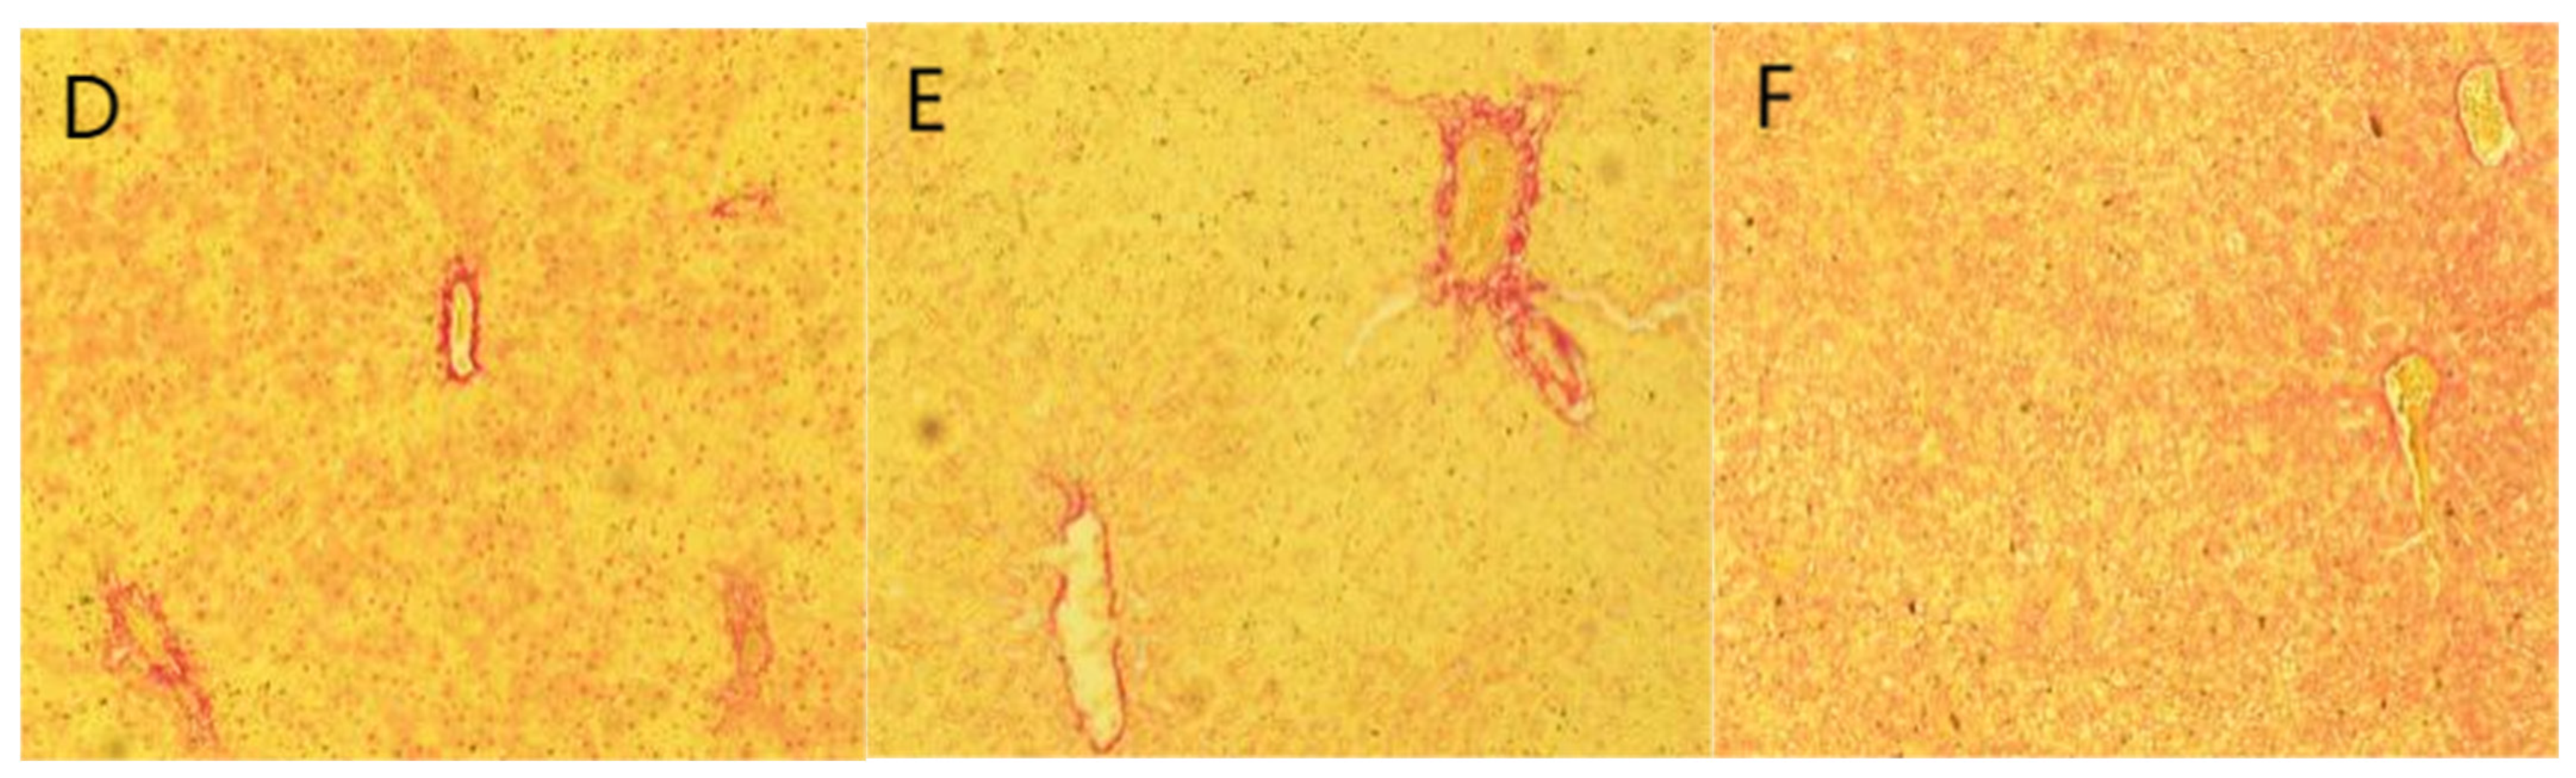

2.6. Staining Results

3.2. Animal Experimentation

4.8. Tissue Embedding Sectioning and Staining